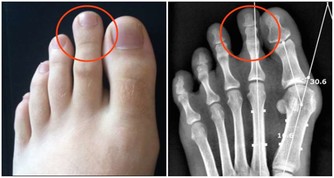

鱉又名甲魚、團魚、元魚、水魚、腳魚等。現代藥理研究,鱉甲可以調節免疫功能,提高淋巴細胞的轉化率,使抗體存在時間延長,增進骨髓造血功能,保護腎上腺皮質功能,防止細胞癌變。臨床實踐證明,吃鱉肉對防治肝癌、腦腫瘤、肺癌、惡性淋巴瘤、胃癌、鼻咽癌和乳腺癌等有一定的作用。